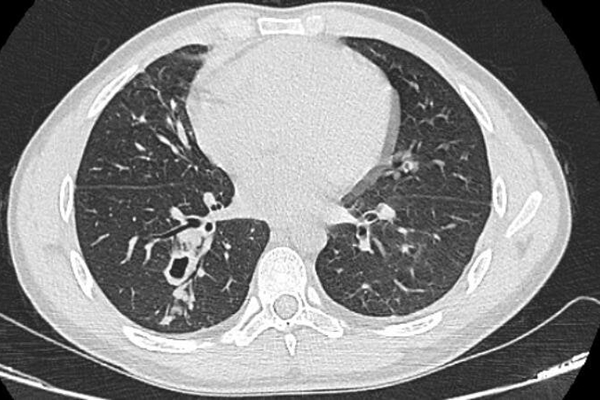

Hình ảnh phim chụp cắt lớp phổi của bệnh nhân sán lá phổi. (Ảnh: BVCC)